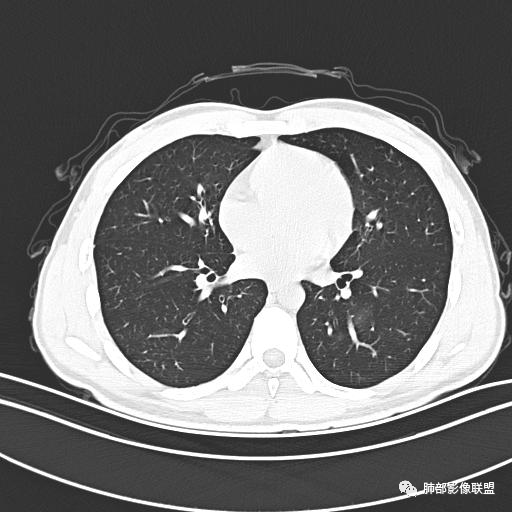

小强:青年,发热,皮疹;双肺散在结节,周围磨玻璃,点晕征,疱疹病毒感染,鉴别荚膜组织胞浆菌,结核。 大雄:青年,急性起病,发热伴全身皮疹2天,抗病毒治疗体温有下降。双肺随机分布大小不等类圆结节,“点晕征”。考虑水痘-疱疹病毒(VZV)血播询问接触史,查体皮疹分布以及形态基本可诊断。 王开金江津中心医院呼吸科:青年男性,起病急,病程短,以发热,皮疹为首发症状,感染指标以单核细胞升高为主,胸部ct双肺多发结界,周围有晕,点晕表现,随机分布,同意於老师意见,水痘疱疹病毒血流感染累及肺。 王秀仙:双肺多发大小不等结节,周围有晕,边缘模糊,呈点晕征表现。青年,急性起病,发热伴全身皮疹2天,抗病毒治疗体温有下降。考虑疱疹病毒。鉴别荚膜组织胞浆菌。 傅昌瑜:19岁男性,发热、全身皮疹2天,单核细胞增高,双肺多发结节,结节边缘见边界不清磨玻璃影。点晕征+发热、全身皮疹+单核细胞增高——考虑水痘-带状疱疹病毒肺炎。 一切∮随缘:年轻男性,发热,皮疹两天,实验室,CRP,PCT增高,影像:双肺多发散在磨玻璃结节,边界欠清,大小不等,呈点晕征改变,以血管束周围分布为主,局部血管束略增粗,其它无明显改变,考虑:1:病毒性肺炎(水痘疱疹病毒?不知道皮肤有无改变)2:真菌(组织胞浆菌,血管侵袭性肺曲霉)3:GPA4:寄生虫(实验室没有看到嗜酸细胞增高) 赵山河:双肺散在结节,周围有晕,边缘模糊,呈点晕征表现。青年,急性起病,发热伴全身皮疹2天,抗病毒治疗体温有下降。考虑水痘—疱疹病毒感染。洪桥爱:青年男性,发热、皮疹2天,伴瘙痒,皮疹于面部首发,之后进展至全身,虽然没有对皮疹进行描述,但是从出疹时间及皮疹进展情况,伴瘙痒,应该就是个水痘患者;CT提示双肺随机分布结节影,部分结节伴有边界不清晕征,考虑水痘血播肺。 刘强:年轻男性,急性起病,皮疹,发热,抗感染治疗体温下降,说明有效。影像表现为散在点晕征,感染类疾病谱(疱疹病毒,真菌,结核),结合年龄,皮肤皮疹,考虑水痘-疱疹病毒性肺炎。 小兜:男性,19岁,发热皮疹两天,颜面部至全身,CRP,降钙素及单核增高。CT示双肺散在小结节,周围伴磨玻璃影,点晕征,考虑为水痘-带状疱疹病毒(varicella-zoster virus,VZV)肺炎 必有路:青年,皮疹+发热+“点晕征”→水痘-疱疹病毒(VZV) 许慧良:青年男性患者,发热、皮疹2天,体温最高38.5℃,第3天皮疹扩展至全身,伴瘙痒,胸部CT:双肺多发随机分布的小结节,结节周边见边界模糊的晕征,考虑水痘病毒感染流心明智:男,19,急性起病,发热伴全身皮疹2天。出疹顺序头→全身,抗病毒有效。胸部CT:两肺多发大小不等类圆形实性小结节影,随机分布,结节周围环绕GGO,边界模糊,呈点晕征。出疹特点是关键,未提示。考虑:血播病毒性肺炎,水痘-疱疹病毒?麻疹?鉴别荚膜组织胞浆菌、TB、血管炎、寄生虫等。 浪迹天涯:病灶多为5-10mm大小结节,结节周围可见磨玻璃样的晕环,常多发,可分布于肺内任何区域,考虑水痘—带状疱疹病肺炎如果短时间内有新的一个区域浸润,更加能说明,